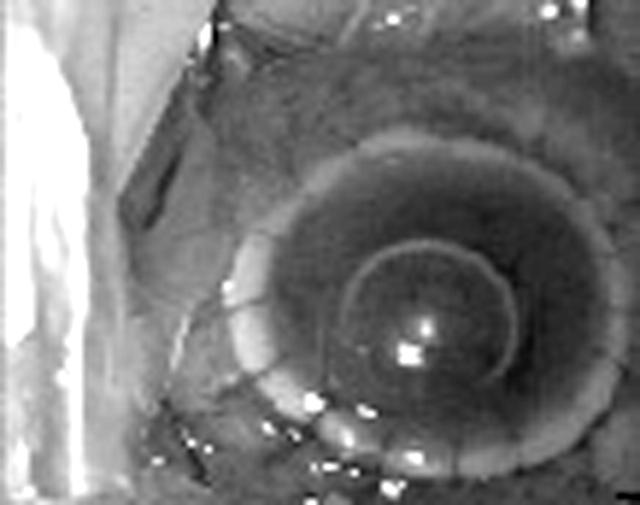

Figure 3.

Clinical photograph showing sloughing of the graft and host cornea.

Figure 4.

Clinical photograph at the completion of therapeutic keratoplasty for the sloughing cornea.